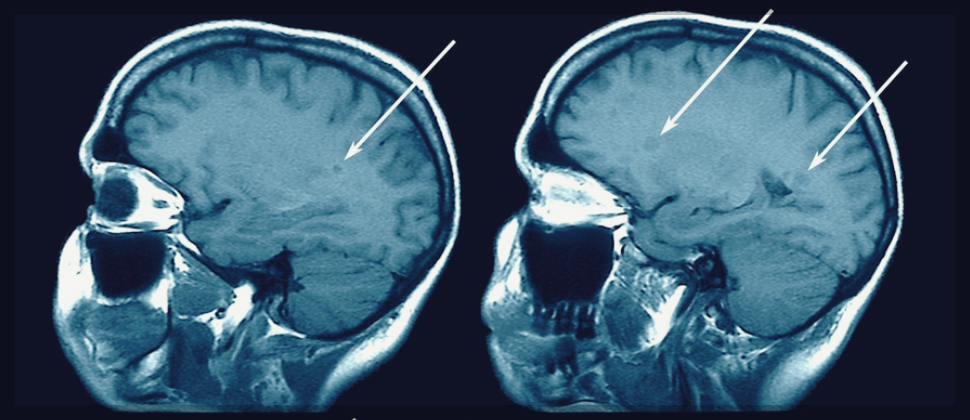

이 질병은 장기간에 걸쳐 뇌와 중추 신경계의 다른 구성 요소를 천천히 악화시키는 퇴행성 특성을 나타낸다. 안타깝게도 이 질병은 호전되어도 다시 재발하는 패턴을 자주 보여준다. 회복 단계로 보이는 동안에도 신경계의 미란, 특히 뇌와 척수의 신경 섬유 주변을 보호하는 미엘린(myelin)이 파괴된다. 이 과정의 영향을 받는 개인은 전반적인 건강과 기능에 좋지 않은 결과를 초래하기도 한다.

일반적으로 뇌와 척수를 포함한 중추 신경계의 여러 부분을 번갈아 침범하면 재발할 수도 있다. 이렇게 침범하면 기존 증상을 악화시키거나 새로운 증상의 유발을 야기시킨다. 이 주기적인 패턴은 신경계의 점진적인 손상 축적에 기여해 궁극적으로 시간이 지남에 따라 심각한 장애로 이어지게 된다. 질병의 재발 특성은 환자에게 중요한 문제이기에 지속적인 관리와 치료 방법이 필요할 것이다.